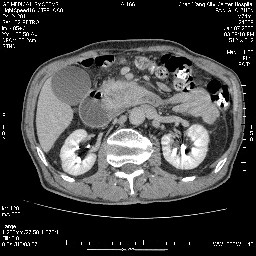

双肾多发小囊肿;左肾积水。

支持十二指肠腺癌伴梗阻.,下腔静脉发育变异.

支持壶腹mt侵及胰腺,那个椎体是骨疝吗???

需除外12指肠水平段间质瘤。

今日手术结果:胰腺钩突癌侵犯十二直肠,腹腔淋巴结转移.